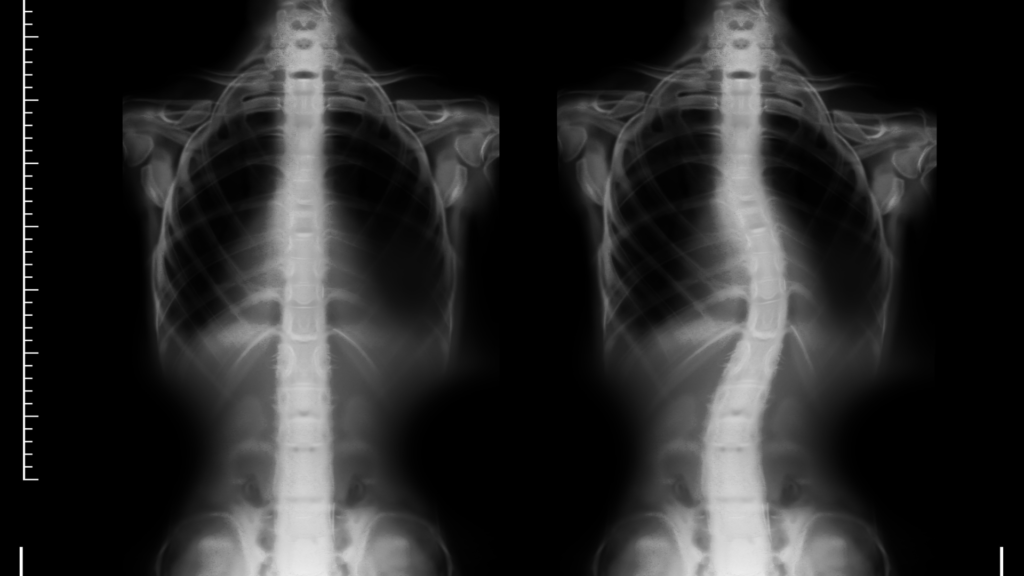

Referência Nacional e Internacional em prática baseada em Evidências Científicas do Tratamento Não-Cirúrgico da Escoliose e Deformidades da Coluna Vertebral.

A Escoliose Brasil nasceu da união dos principais pesquisadores e especialistas do país em tratamento não-cirúrgico da escoliose. Com metodologia própria publicada no The New England Journal of Medicine e mais de 20 turmas de profissionais formados em 14 estados, somos referência nacional e internacional.

O Método S4D foi desenvolvido pela equipe de especialistas da Escoliose Brasil e representa o que há de mais avançado no tratamento conservador da escoliose. O nome vem dos quatro pilares: Spine (coluna), Support (suporte), Strengthening (fortalecimento) e Dynamic (dinâmico).

O Método S4D foi desenvolvido por pesquisadores brasileiros com base em evidências científicas internacionais. Tem taxa de sucesso de 85-90% em casos qualificados, comprovada em estudos publicados em revistas de alto impacto.